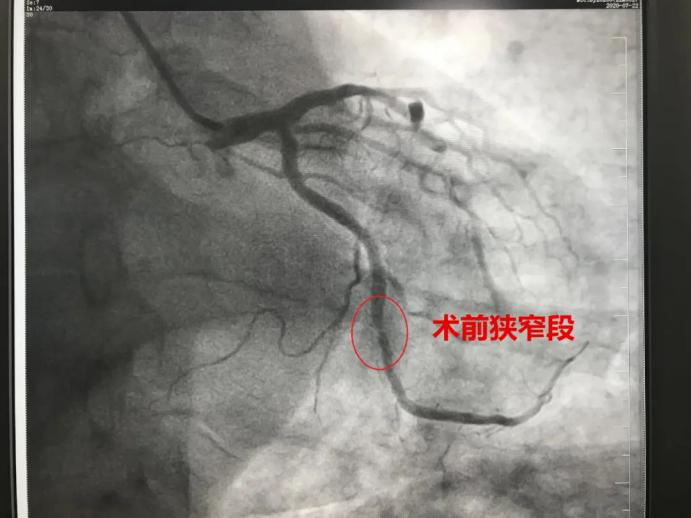

东南医院|上新台阶!重庆市东南医院首例心脏冠脉造影和心脏支架植入术成功开展

近年来 , 冠脉疾病逐年增高并呈年轻化趋势 , 经前期充分准备 , 重庆市东南医院心血管内科于7月22日成功开展3台冠脉造影、2台冠状动脉支架植入术 。 据悉 , 心脏介入手术在该院为首次开展 , 手术的成功标志着医院心血管内科介入技术迈上新台阶 。

专家称 , 冠心病的病理生理基础是冠状动脉狭窄 , 根据冠脉狭窄程度以及动脉粥样硬化斑块稳定性的不同 , 冠心病有不同的临床表现 , 包括劳力型心绞痛、不稳定型心绞痛、非ST段抬高性心肌梗死和ST段抬高性心肌梗死 。

冠状动脉造影可为冠心病诊断提供可靠的解剖和功能的信息 , 为评价预后、介入治疗或冠脉搭桥术方案的选择奠定了科学依据 , 是诊断冠心病的“金标准” 。

(术后前后对比)